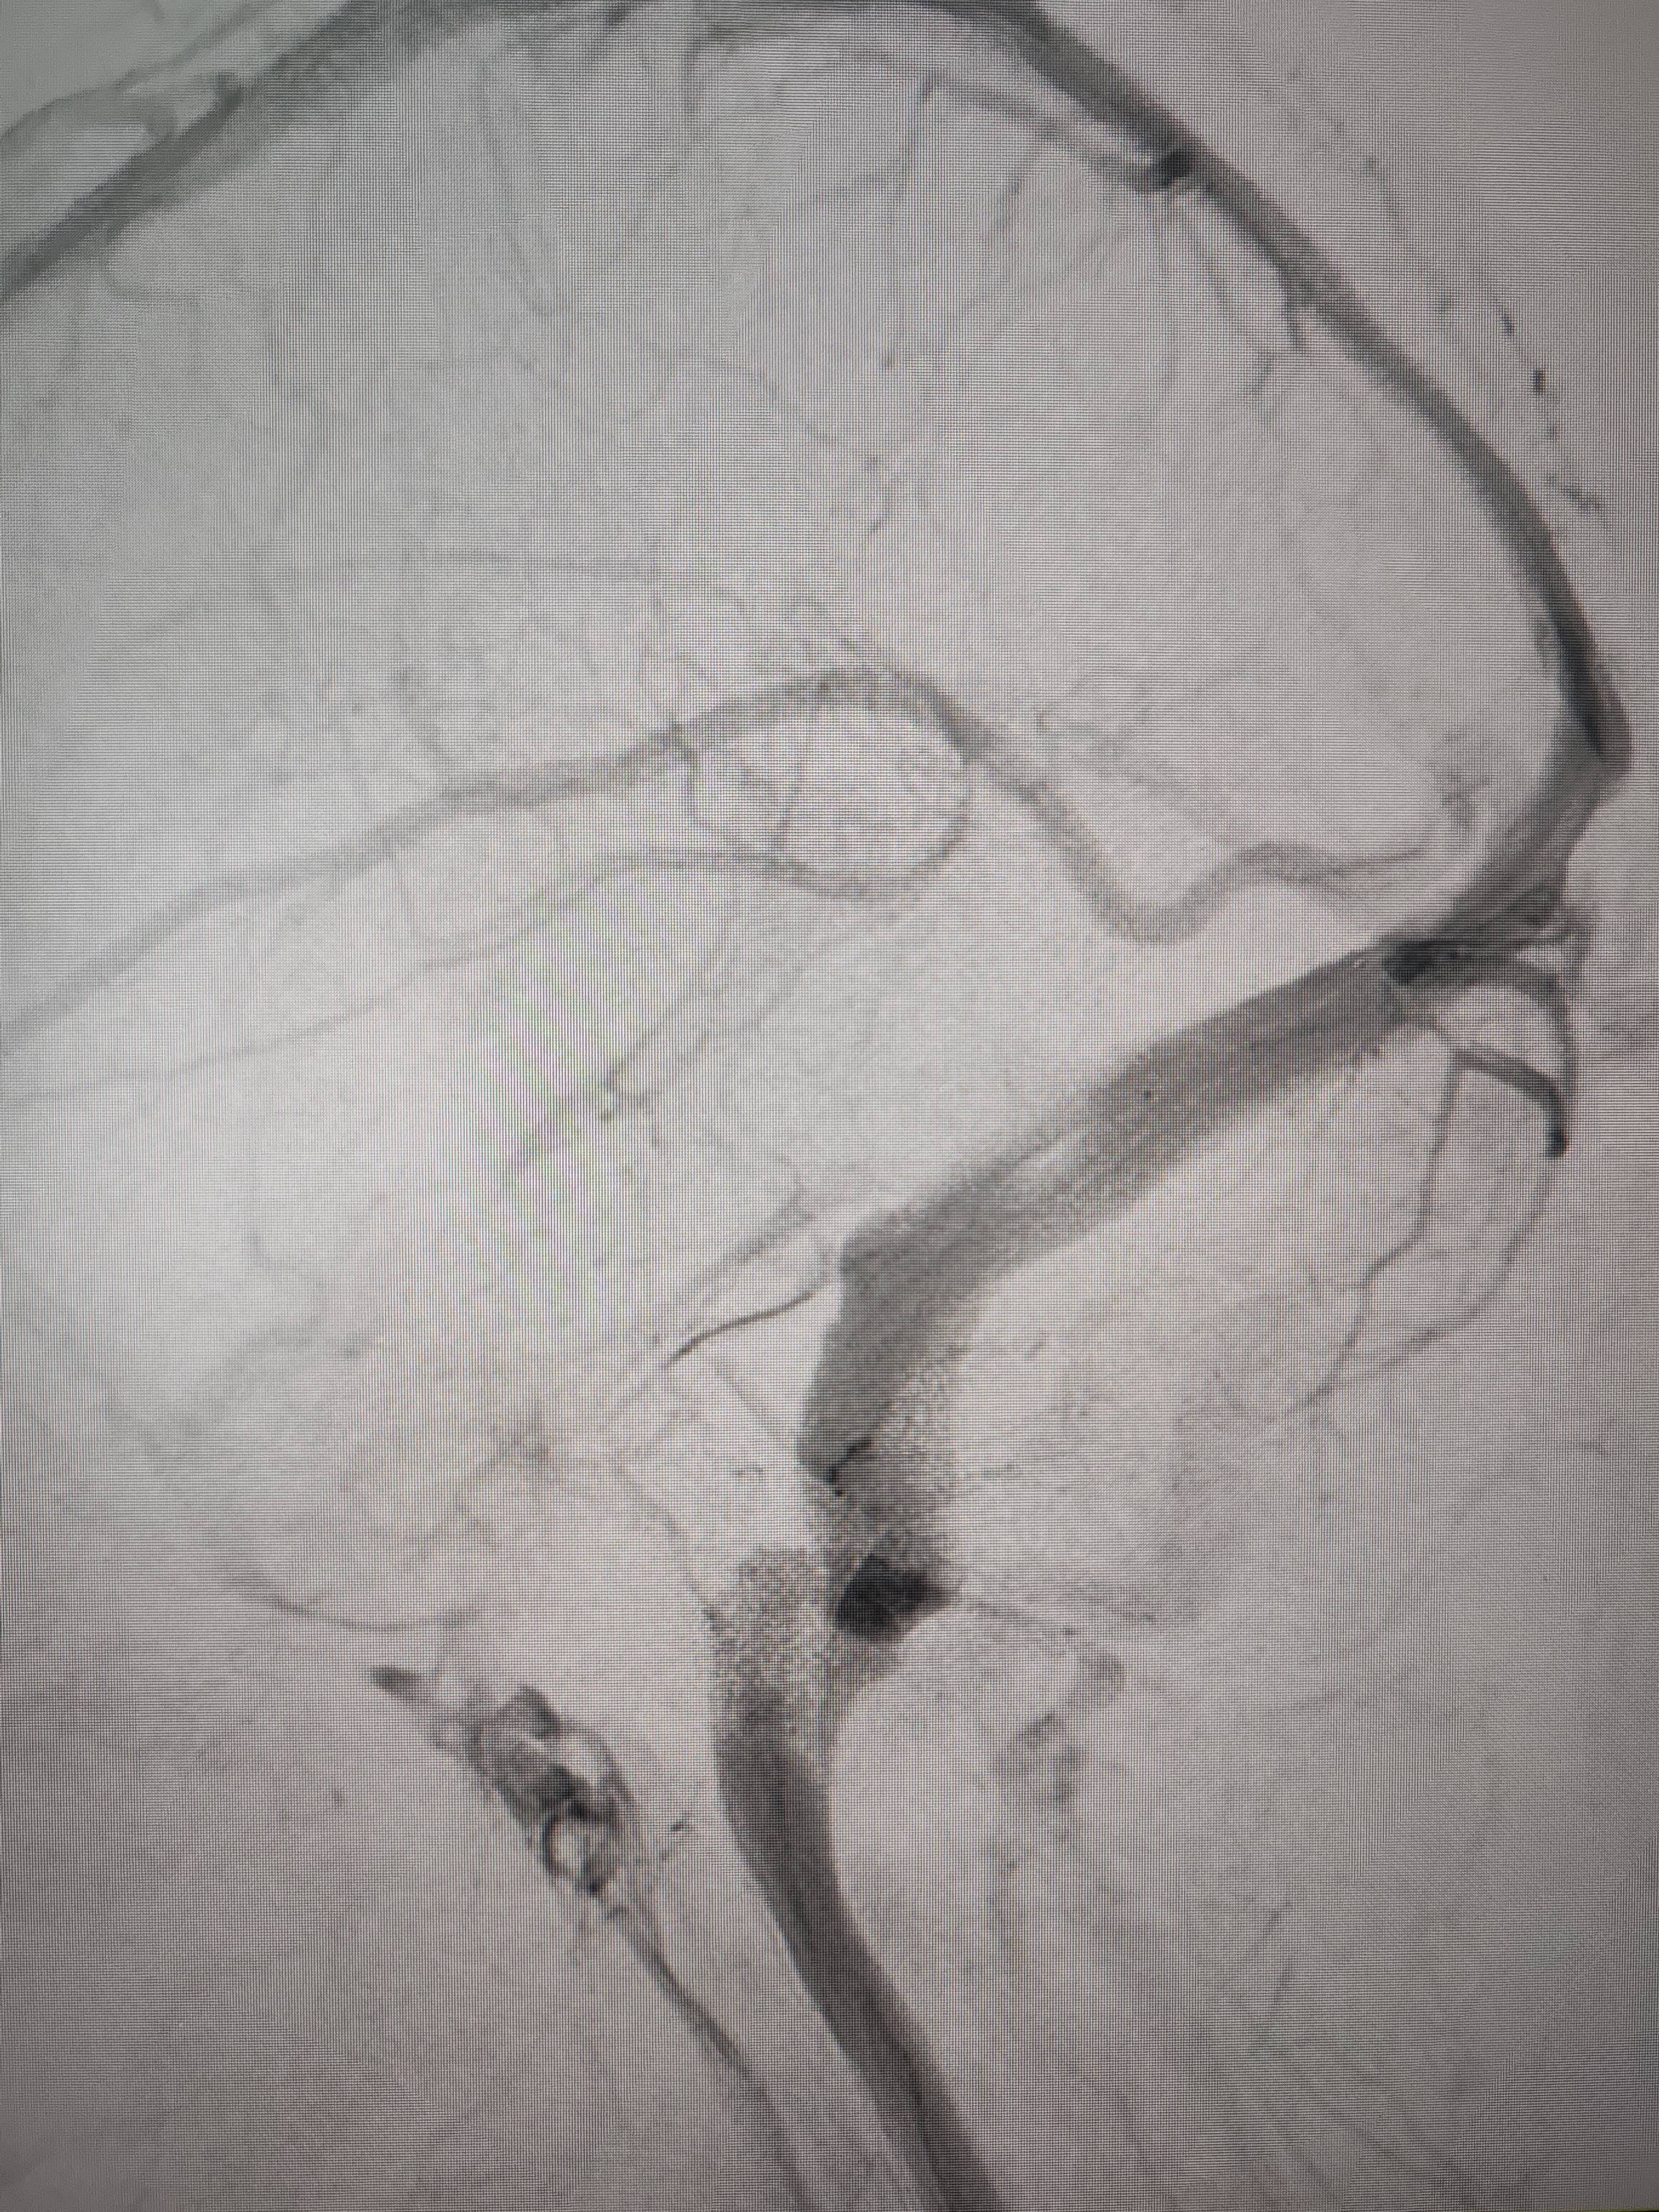

经过静脉窦支架置入手术治疗后,患者的静脉窦“堵点”被打通抹茶交易。 南方+ 欧阳少伟 拍摄